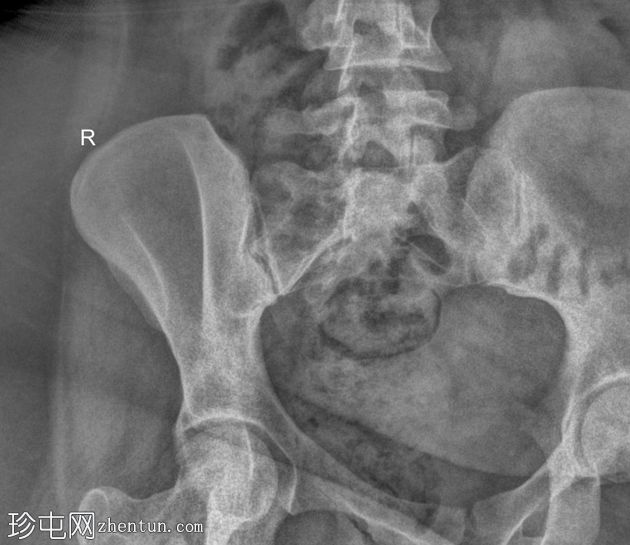

病例介绍

类

风湿

性关节炎伴腰痛。

患者资料

年龄:35岁

性别:女

斜位

骶髂关节正位和斜位X线片显示正常。